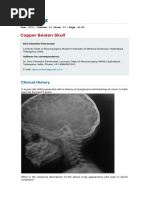

Appearance of beaten metal copper on plain radiography.

Copper Beaten Appearance - Initial radiographs of the skull showed a copper beaten appearance, indicating chronically elevated intracranial pressure.

Copper beaten skull was an incidental finding in the patient. In infants and young children pulsations from the rapidly growing brain can produce markings on the inner table of the skull forming a peculiar pattern, variously described as beaten silver appearance or, more commonly, copper beaten appearance. This is seen due increased to the prominence of convolutional markings or gyral impressions of the brain on the inner table of the skull seen throughout the skull vault. The significance of beaten copper appearance (bca) on skull radiographs in children following surgery for isolated sagittal craniosynostosis has not been studied. The beaten copper pattern originates from the pressure that the brain exerts on the continuously remodeling inner cranium resulting in bony convolutions that are manifested as a beaten copper appearance on cranial radiographs. Acute nch will present with headaches, neurologic changes, nausea, and vomiting and if left untreated may lead to coma or death. Initial radiographs of the skull showed a copper beaten appearance, indicating chronically elevated intracranial pressure. Convolutional markings may be normal but are usually confined to the posterior part of the skull's inner table. A significant difference between acute and chronic nch is the clinical presentation. However, the copper beaten appearance of the skull has poor sensitivity in detecting increased intracranial pressure as such an appearance can also be seen in normal patients. Prominent convolutional markings of the skull may be first seen at approximately 1 year of age, and their persistence until the 13th year of life is not uncommon. Copper beaten appearance of bones of cranial vault is also noted click here to view figure 6: Ing surgery for isolated sagittal craniosynostosis has not total of 28.6% (n=6) of the children with follow up been studied.